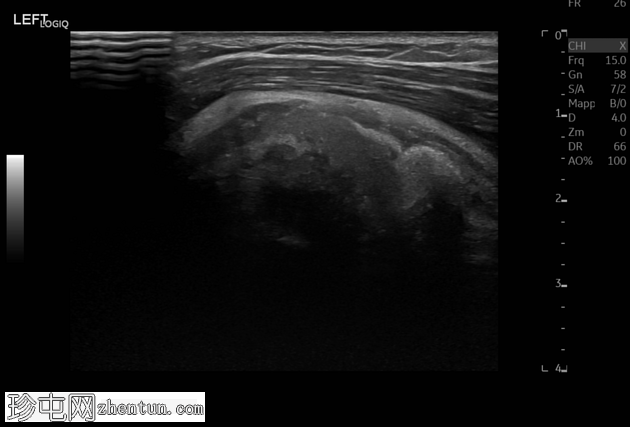

超声

轴位

肩峰下滑囊-三角肌下滑囊积液内可见轻度高回声、不均匀的钙化灶,无声影(“浆液状钙化”)。滑囊壁增厚,周围脂肪间隙水肿。

在吸收期,钙沉积物几乎呈液态,这种情况可能因钙沉积物从肌腱纤维(通常是冈上肌)迁移至肩峰下间隙、肩峰下滑囊或肱骨大结节而变得复杂,从而引起剧烈疼痛和活动范围受限。